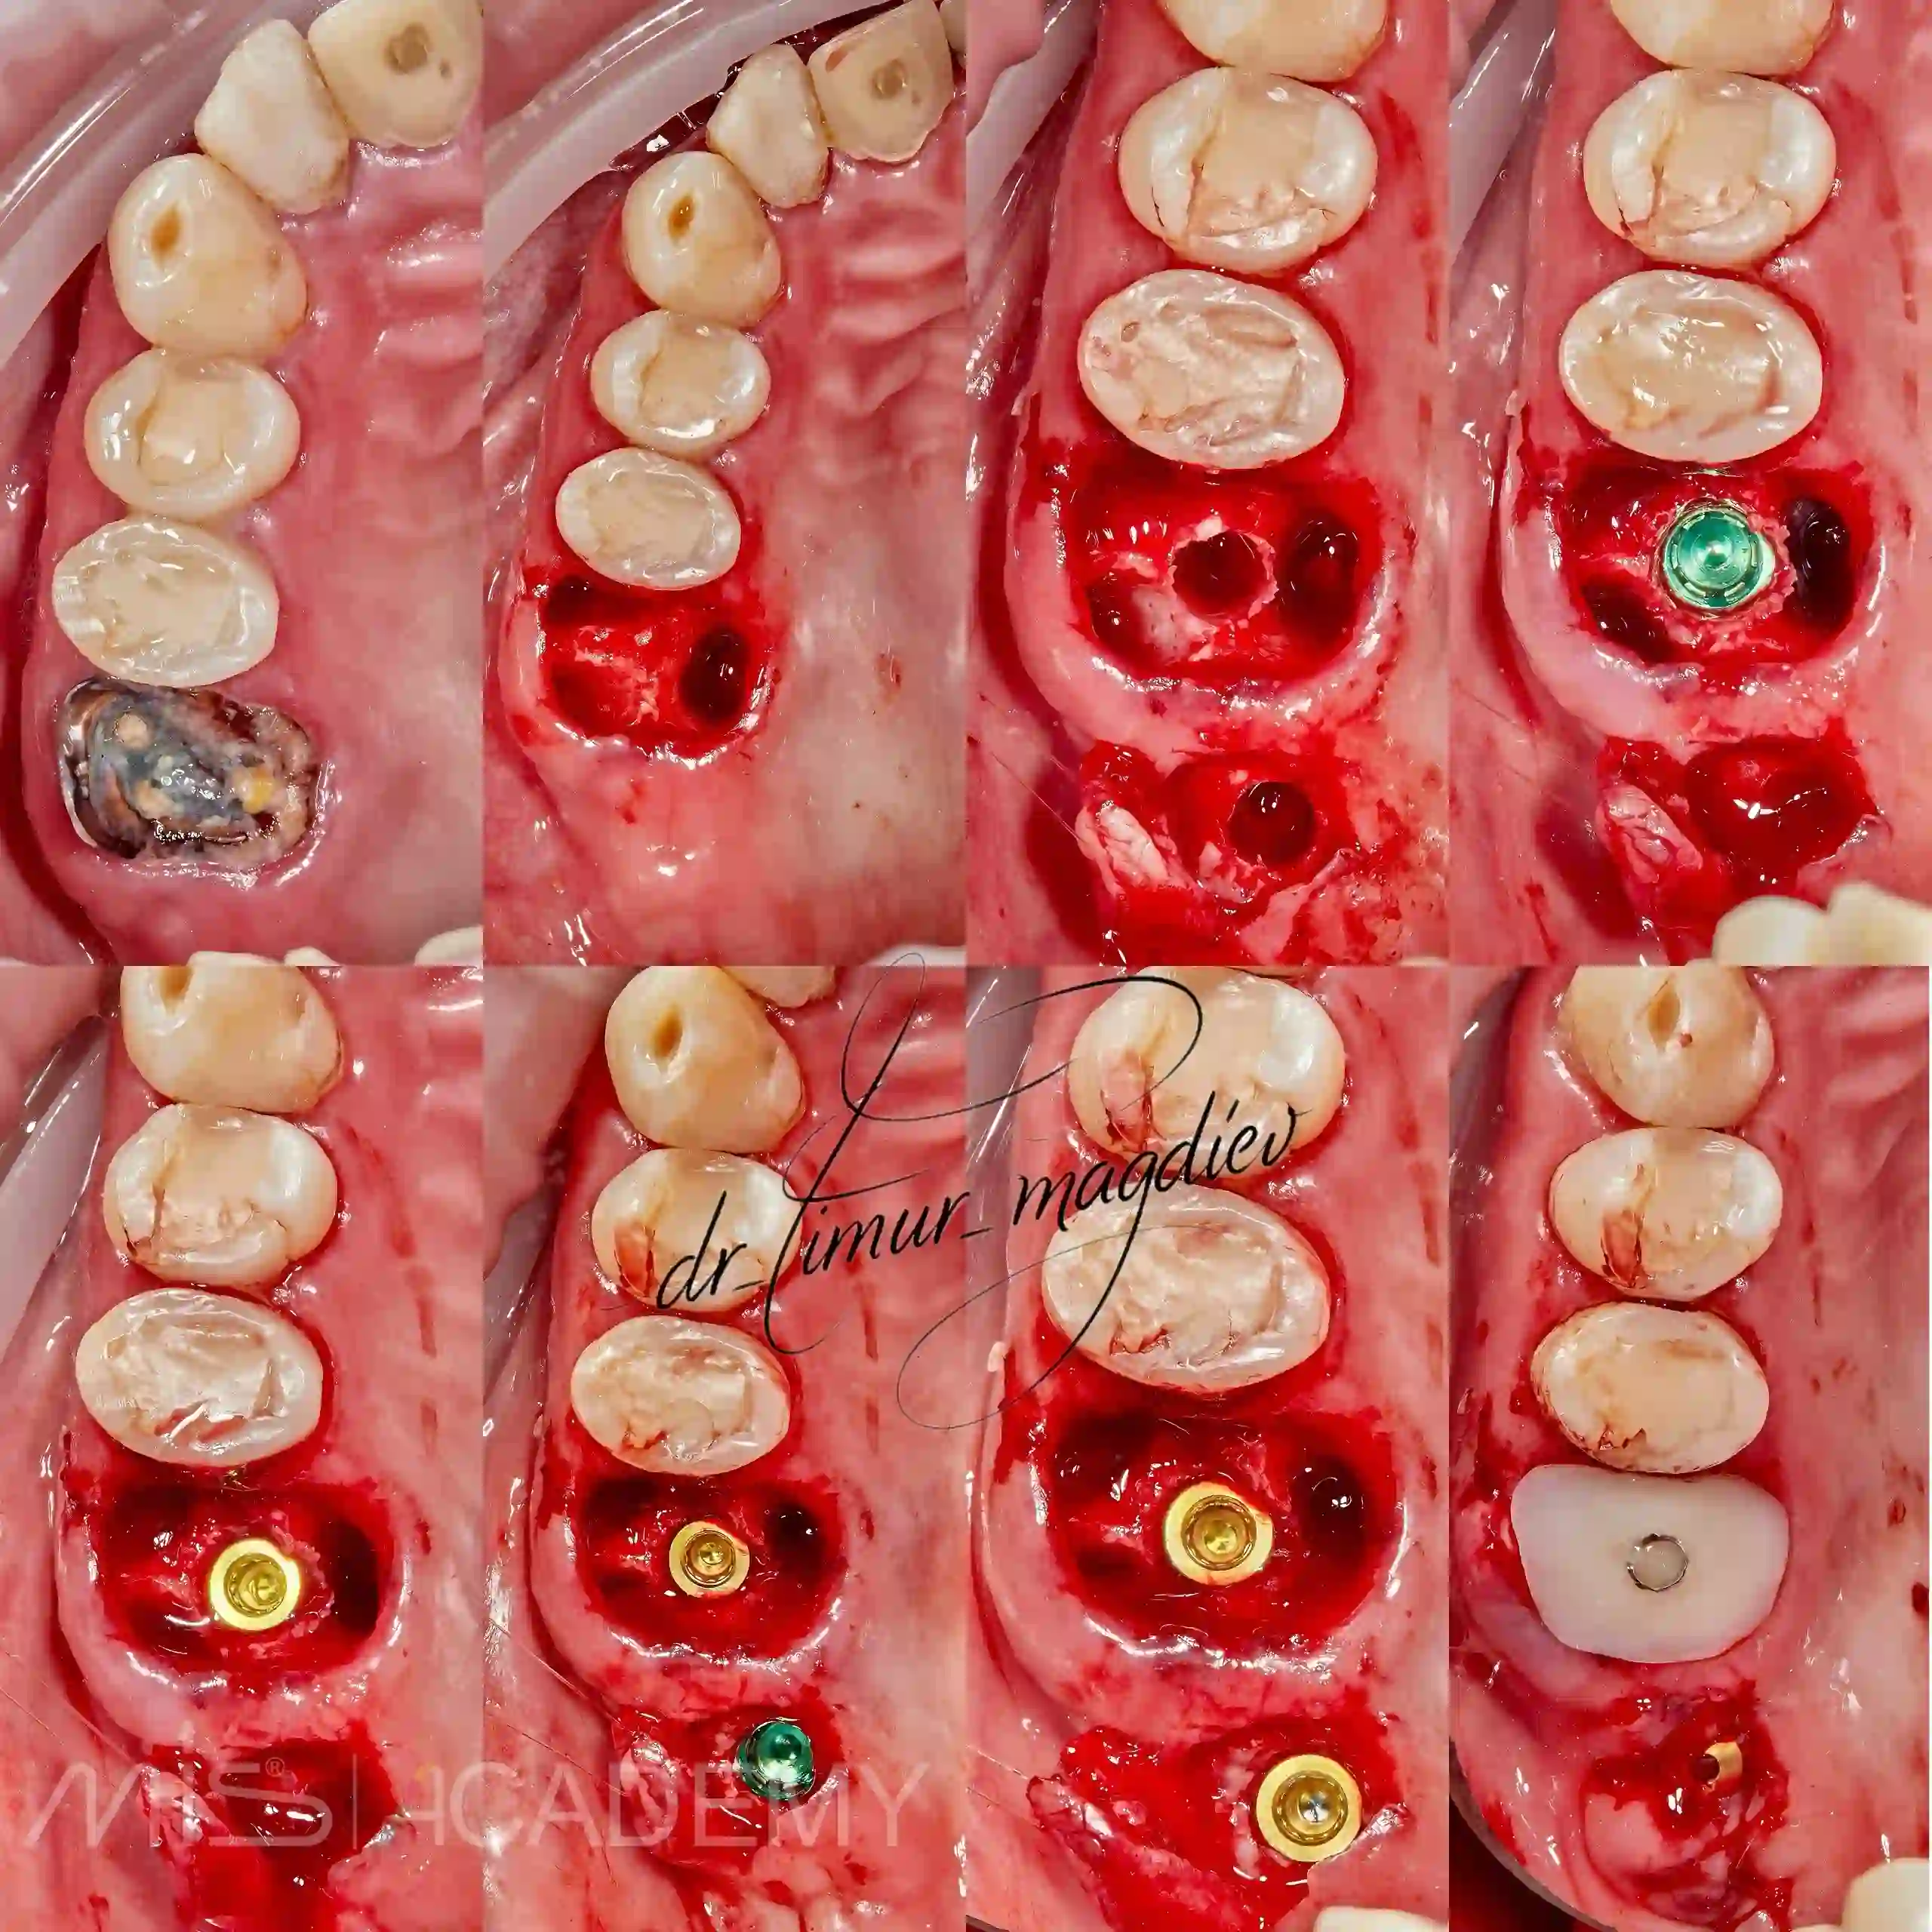

— Имплантация MIS C1 + Connect.

— Благодаря навигационной хирургии установили имплантаты без ОСЛ.

— Закрытый кристальный синус.

— Работа с мягкими тканями.